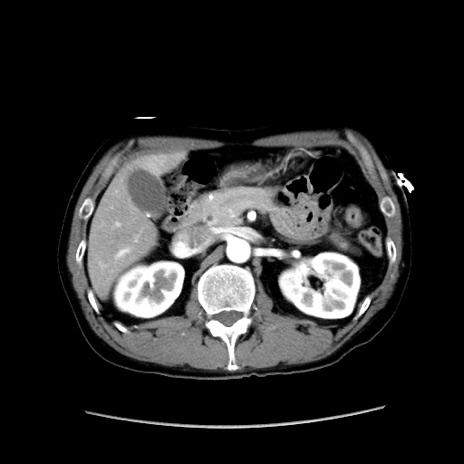

症例37(横断像)

【症例】40歳代 男性

【主訴】腹痛

【現病歴】4時間ほど前に電車に乗車中に臍部上より腹痛出現。徐々に増悪し起立困難となり、救急外来受診。生ものは数日食べていない。今朝お雑煮を食べた。

【身体所見】BT 36.8℃、BP 117/84mmHg、HR 91/min、SpO2 97%、苦悶様、腹部:臍上部広範囲圧痛あり、反跳痛±

【データ】WBC 8100、CRP 0.03